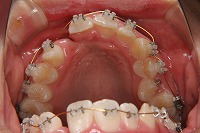

反対咬合を主訴に来院された、右側唇顎裂の10歳6ヵ月の女の子です。診断「右側唇顎口蓋裂で反対咬合を伴う」1期治療で反対咬合の解消と上顎の前歯の並びを修正しました。2期治療は抜歯をせず治療を行いました。